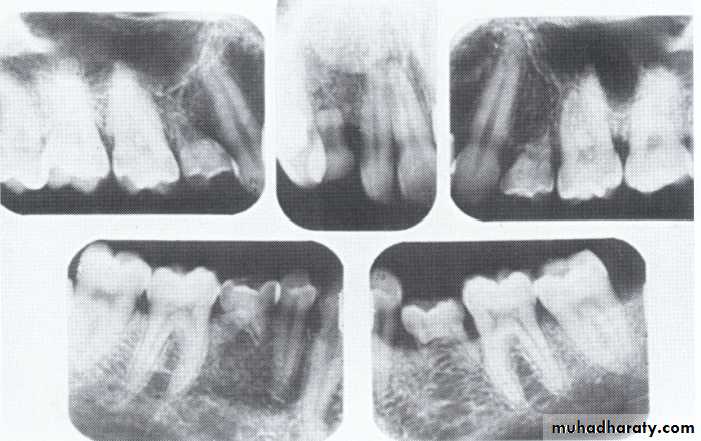

• Fusion of the left mandibular central and lateral incisors (twoindividual roots, two root canals and two joined crowns).

Gemination of right mandibular central incisor has one root, one root canal and a partially bifid dental crown.